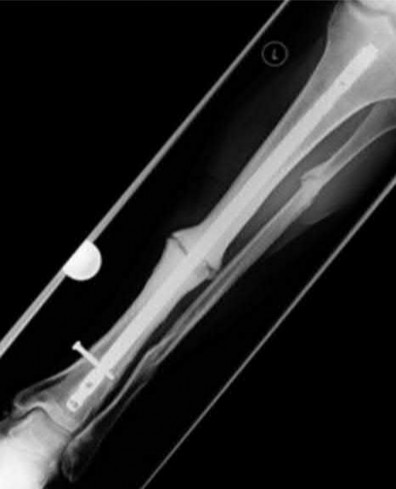

A 32-year-old male sustains a closed tibia fracture and develops intense leg pain out of proportion to the injury. You suspect acute compartment syndrome.

Which of the following pressure parameters is considered the most reliable threshold indication for performing a four-compartment fasciotomy?

Explanation

The differential pressure (Delta P) is universally recognized as more reliable than absolute compartment pressure for diagnosing acute compartment syndrome. A Delta P is calculated by subtracting the intracompartmental pressure from the patient's diastolic blood pressure. A Delta P of less than 30 mmHg represents inadequate tissue perfusion pressure and is an absolute indication for emergency fasciotomy.